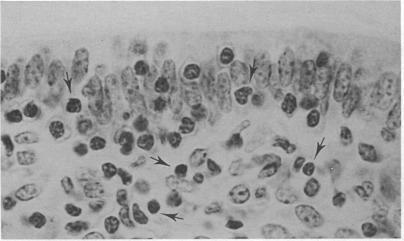

A panel of monoclonal antibodies was used to define the lymphocyte subpopulations in the sheep uterus at various stages of the oestrous cycle. A striking finding was that the majority of lymphocytes in the uterine and endometrial glandular epithelia belonged to a unique lymphocyte subpopulation that expressed the CD45R antigen but was negative for major histocompatibility complex (MHC) class II molecules and expressed low or undetectable levels of the CD5 antigen. When examined under the electron microscope using the immunogold technique, the CD45R+ lymphocytes were found to have one to three membrane-bound granules in their cytoplasm. Other lymphocyte subpopulations found in the uterus at various stages of the oestrous cycle were localized mainly in the caruncular and intercaruncular stroma. The unique CD45R+ granular lymphocyte subpopulation may be equivalent to the 'natural killer' cells reported in mouse and man, and may have an important role in local immunity of the female reproductive tract.

一组单克隆抗体被用于确定发情周期不同阶段绵羊子宫中的淋巴细胞亚群。一个显著的发现是,子宫和子宫内膜腺上皮中的大多数淋巴细胞属于一个独特的淋巴细胞亚群,该亚群表达CD45R抗原,但主要组织相容性复合体(MHC)II类分子呈阴性,且CD5抗原表达水平低或检测不到。当使用免疫金技术在电子显微镜下检查时,发现CD45R+淋巴细胞的细胞质中有一到三个膜结合颗粒。在发情周期不同阶段子宫中发现的其他淋巴细胞亚群主要位于肉阜和肉阜间基质中。独特的CD45R+颗粒淋巴细胞亚群可能等同于在小鼠和人类中报道的“自然杀伤”细胞,并且可能在女性生殖道的局部免疫中发挥重要作用。